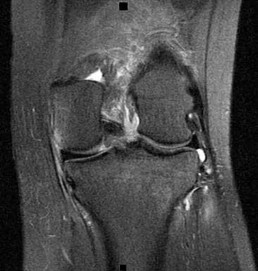

A 22-year-old man sustains an injury to his right knee in a motor vehicle collision. Figure 22a is the posterior stress radiograph of the involved knee, and Figure 22b is a selected MR image that identifies the injured structure.

CLINICAL SITUATION FOR QUESTIONS 22 THROUGH 25

The stress radiographs demonstrate posterior instability of the right knee in flexion. The MR images demonstrate injury to both the anterior and posterior cruciate ligament (PCL), with the stump identified with the arrow on the MR image (Figure 22b). The PCL has 2 functional bands. The anterolateral bundle originates from the roof of the intercondylar notch. It runs in a posterolateral direction onto the tibial crest between the posterior attachment of the medial and lateral menisci. During a double-bundled posterior ligament reconstruction, the

anterolateral bundle is tensioned with the knee in a position of mid flexion. The posteromedial bundle has a variable pattern of tension both in extension and in high flexion. Tensioning of the posteromedial bundle in extension may contribute to resistance against knee hyperextension.

The meniscofemoral ligaments are variably present. Although 93% of knees have been reported to have at least 1 meniscofemoral ligament present, both ligaments are simultaneously present in approximately 50% of knees. The ligament of Humphrey (anterior meniscofemoral ligament) and ligament of Wrisberg (posterior meniscofemoral ligament) are delineated by their anatomic relationship to the posterior cruciate.